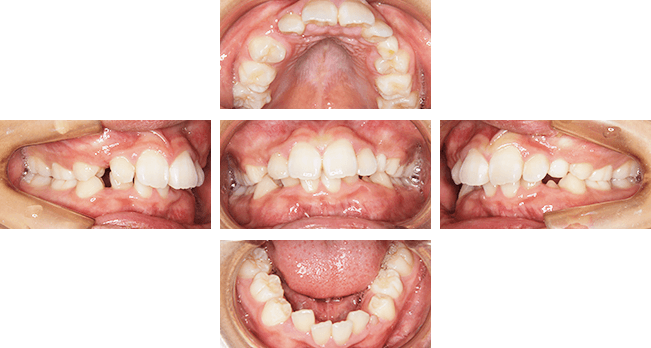

上顎前突case1. 10代女性(治療期間4年11か月)

| 主訴 | 前歯が出ている(審美障害) |

| 診断名 | 上顎前突、過蓋咬合、空隙歯列弓 |

| 初診時年齢 | 9歳5か月 |

| 性別 | 女性 |

| 動的治療期間 | 4年11か月 |

| 主な矯正装置 | 咬合斜面板、アクティブプレート、ヘッドギア、マルチブラケット装置 |

| 抜歯/非抜歯 | 非抜歯 |

| 治療費用(税込) | 検査診断:44,000円 装置料:550,000円 調節料:5,500円×54回 |

| 副作用とリスク | 成長期からの治療(早期治療)になるので、治療期間が長くなります。そのため、患者さんの協力が非常に重要になります。 |

治療前